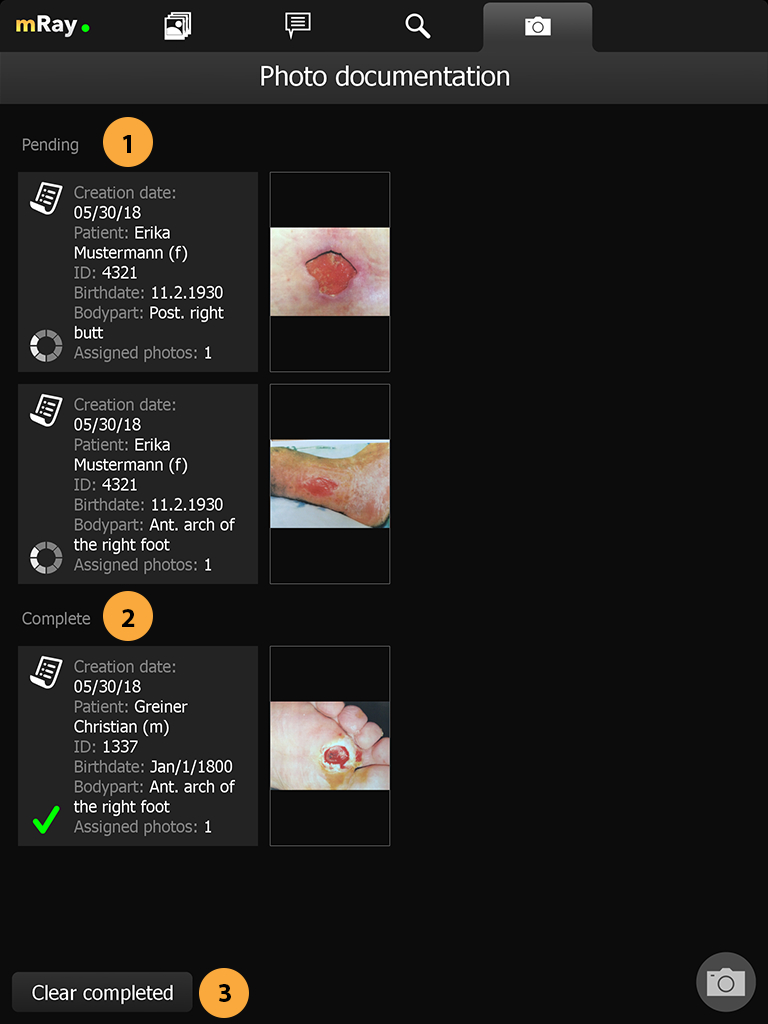

15.7. Assigned view

This view is the default view when you press the photo documentation tab in the top. It is an overview that lists all unassigned photos, pending orders and completed orders. By pressing the unassigned photos (Point 1) you’ll proceed into the review gallery where you can assign those photos like already described above. The list of pending orders (Point 1) are the orders that have not yet been confirmed by the server. This can be caused by no internet connection or that the server is still processing those orders. The completed list (Point 2) shows all orders that are known to be completely processed. By pressing the "Clear completed" button (Point 3) those orders are not shown anymore to you.

-

List of pending orders that are uploading or waiting for approval.

-

List of completed orders.

-

Button to clear the list of completed orders.